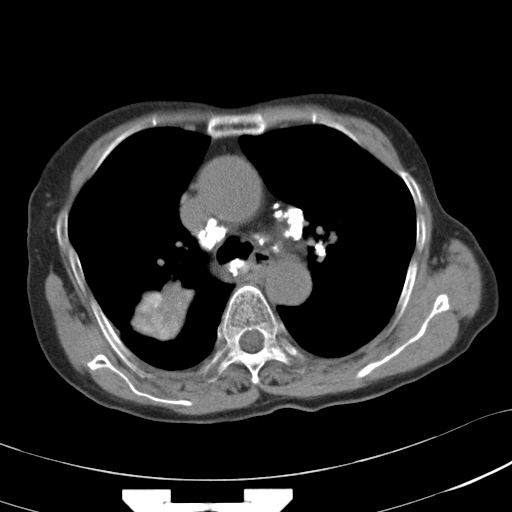

以下是引用hhcckk在2007-3-2 14:51:00的发言:[br]考虑结核球可能性大,依据[br]1病灶在下叶背段,结核的好发部位[br]2病灶内有大量的钙化,纵隔内有大量的淋巴结钙化[br]3重要的是半年前与现在相比无变化,假如是肿瘤的话不会这么‘善良’[br]4病灶周围卫星灶不明显,病灶有毛刺,胸膜凹陷,肿瘤不能完全排除,有条件的话最好做个活检

以下是引用liuyue在2007-3-2 17:15:00的发言:[br]1位置:右上叶后段[br]2性质:大分叶、粗长毛刺、条状斑片状钙化、纵隔多发淋巴结钙化,无强化,故考虑:肺结核灶(陈旧)